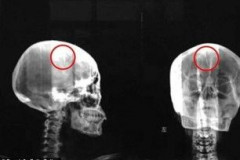

Չինուհին 46 տարի ապրել է` 4.5 սմ երկարությամբ ասեղը գլխում